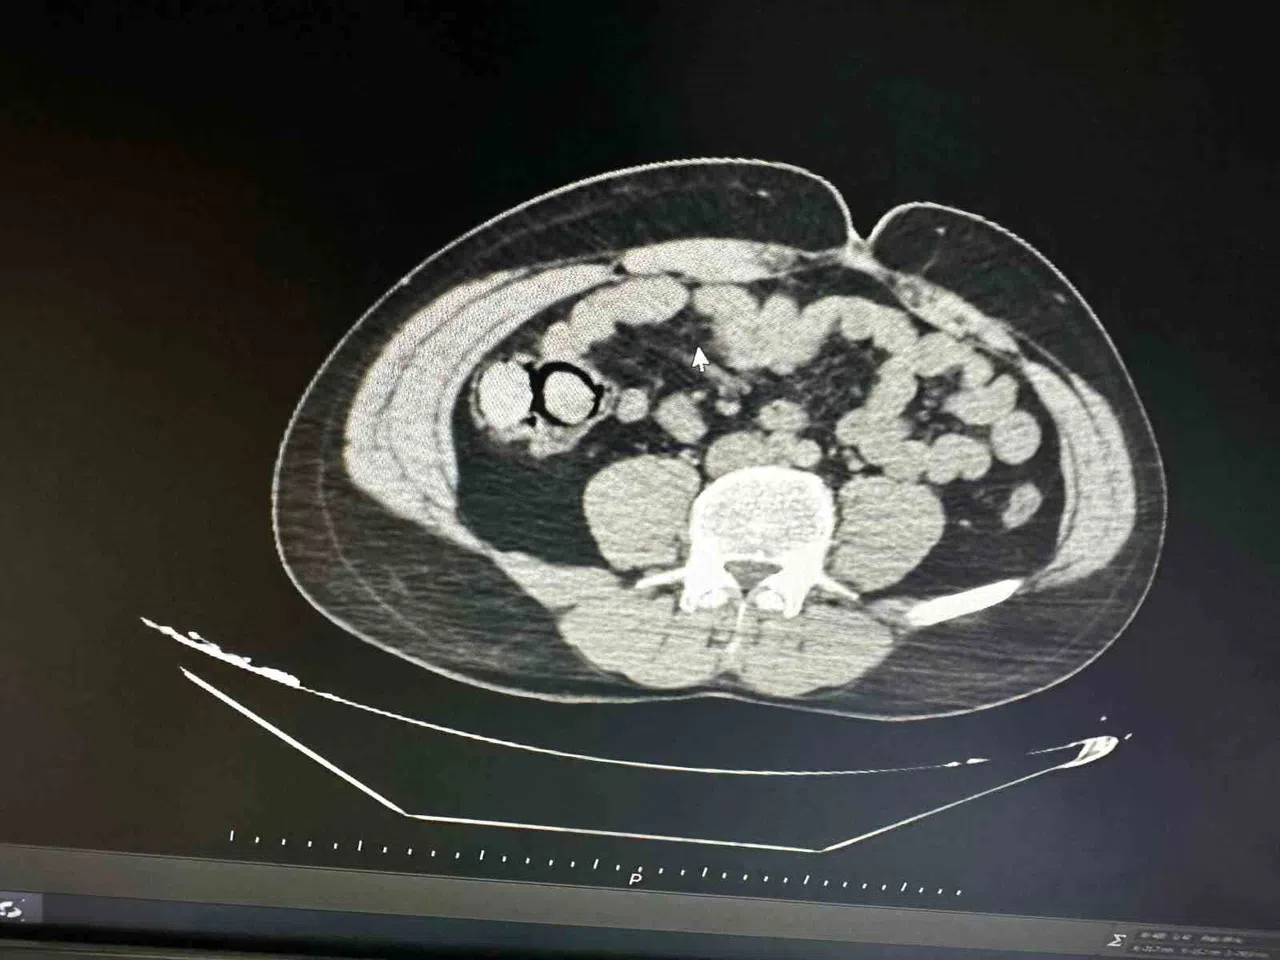

Bingöl Emniyet Müdürlüğü Narkotik Suçlarla Mücadele Şube Müdürlüğüne bağlı narko-timleri akıllara durgunluk veren bir uyuşturucu kaçakçılığını çözdü. Ekiplerin çalışmaları neticesinde otobüs ile Bingöl’e gelen şüpheli yabancı uyruklu 2 şahsın iç beden muayenesinde 10 parça halinde 113 gram metamfetamin maddesi tespit edildi. Emniyetteki işlemlerinin ardından mahkemeye çıkarılan 2 şahıs, uyuşturucu madde ticareti yapmak suçundan tutuklanarak Elazığ Kapalı ceza infaz kurumuna teslim edildi.